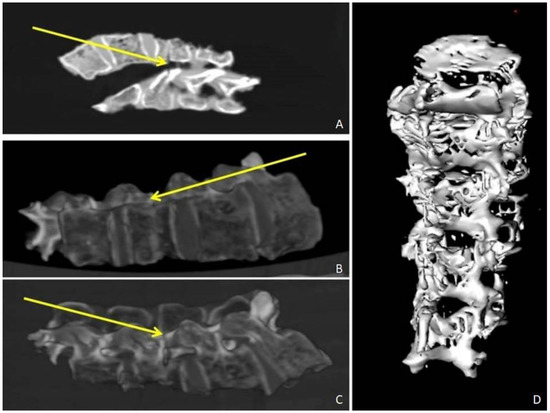

2.3. PMCT Finding

Before the autopsy, PM-CT was carried out on 128-section multidetector CT scanners (Somatom Definition AS, Siemens Healthcare, Erlangen, Germany). The CT protocol consisted of a single total-body acquisition (nominal thickness 0.625 mm, reconstruction thickness 0.625 mm, and 1.25) In case 1, the three-dimensional CT reconstruction showedthe presence of shearing lesions at the level of the third lumbar vertebrae and the disruption of the cortical bone at the vertebral processes (Figure 1). In case 2, total-body CT scan showed multiple fracture rims with clean margins of the neurocranium, upper and lower limb fractures, multi-fragmented fracture of the right zygomatic bone and the nose, and fracture of the sternum; right costal fractures of II, IV, V, VII, and VIII;fracture of the right iliac spine, the right sacral half, the ischial branches, and the pubic bones bilaterally (Figure 2 and Figure 3). PMCT permitted to distinguish traumatic from heat fractures.

Figure 1. Case 1. PMCT Coronal plane reconstruction. (AC) Axial PMCT planes show disruption of the cortical bone at the vertebral processes (yellow arrows). (D) Three-dimensional volume rendering reconstruction.